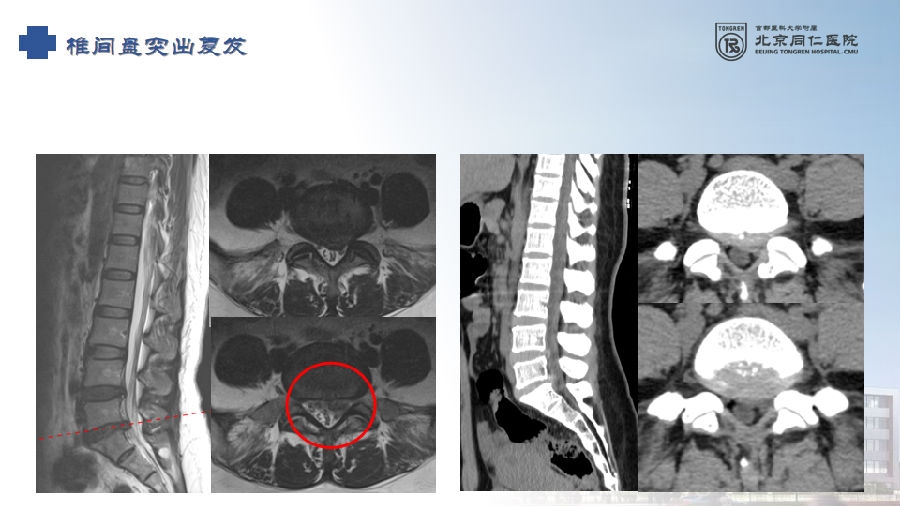

六、复发(2.27%)

病例(椎间盘突出复发)

女,42岁。

主诉:腰痛伴左下肢疼痛2月。

查体:疼痛放射至左侧臀部、大腿后侧、小腿后外侧。

思考和建议

完整切除突出的椎间盘

切除的椎间盘为影像学体积150%

视情况缝合纤维环,避免复发